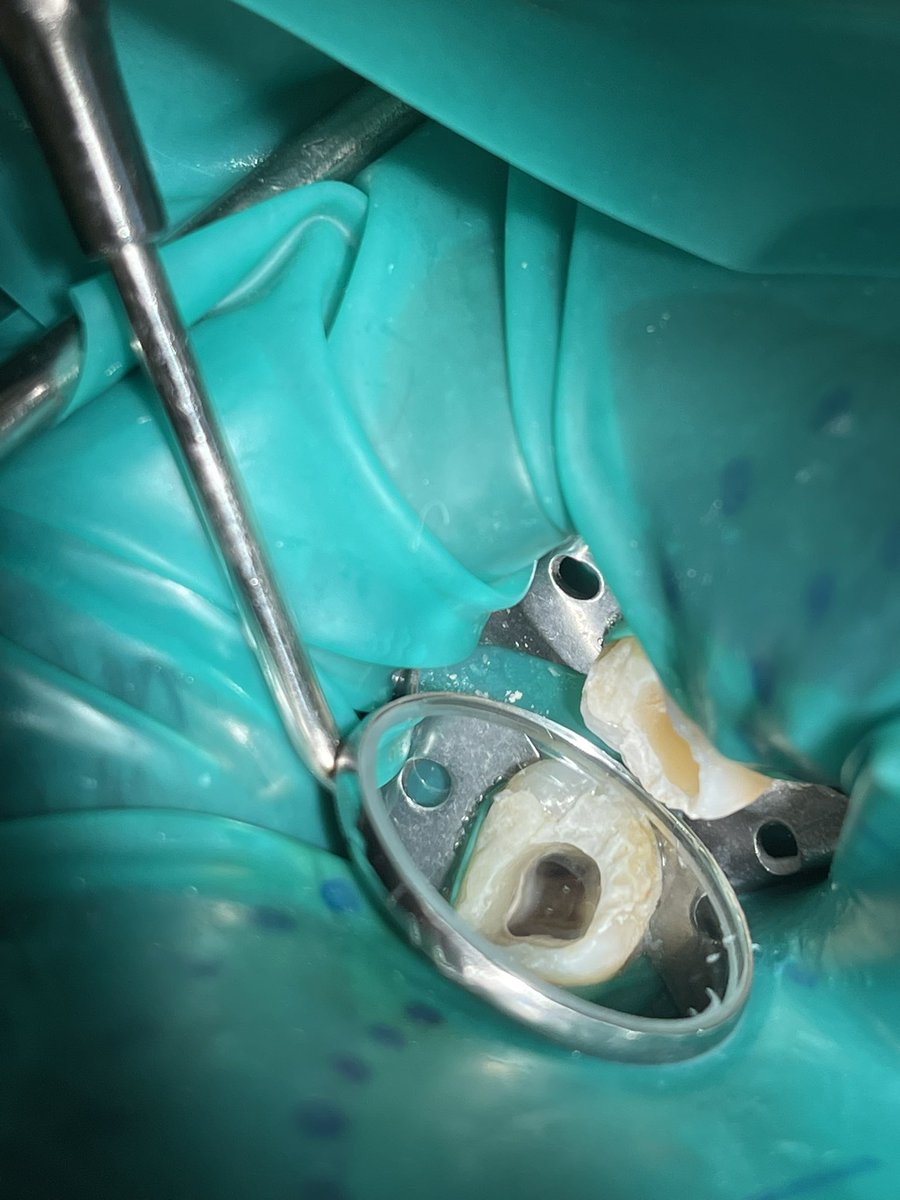

#47🦷

Dx:

Symptomatic irreversible pulpitis with symptomatic apical periodontitis

Tx:

RCT followed by TF